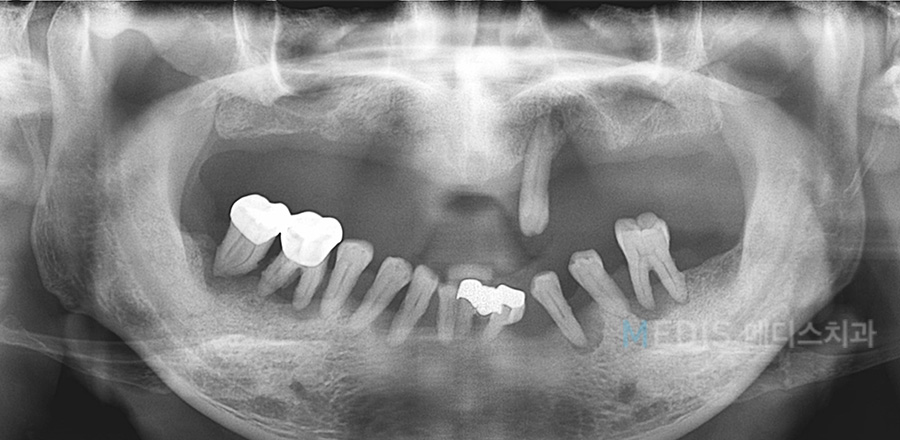

[임플란트] 전체 임플란트 식립 사례

전체 임플란트 식립 전

※ 치료기간 : 2016.12.05~2017.09.01

(치료 기간은 환자분의 협조도 이에 따라 달라질 수 있습니다.)

※ 부작용 : 환자의 경향에 따라 통증, 부종과 멍 등의 부작용이 생길 수 있습니다.

*상기 사진은 본원에서 치료를 받은 분의 동의를 얻은 사진으로 실제와 차이가 있을 수 있습니다.

* 상기 사진은 본원에서 동일한 인물이 동일한 조건에서 촬영하였습니다.